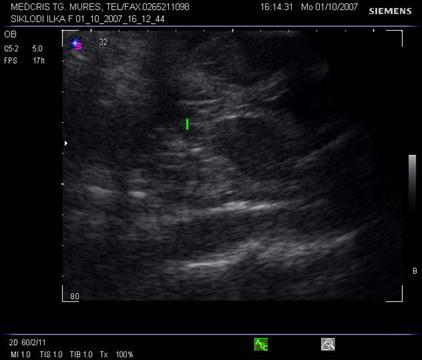

Vezica urinara se poate identifica de la 12 saptamani transvaginal, zona rotunda anecogena in pelvis, nu ar trebui sa depaseasca 6 cm in diametru pana la terminarea sarcinii. Este marginita de oasele iliace in sectiunile longitudinale sau oblice. Vezica urinara trebuie obligatoriu identificata prin examene ecografice repetate, in caz contrar se ridica suspiciunea unor malformatii.[ 1,8,13]